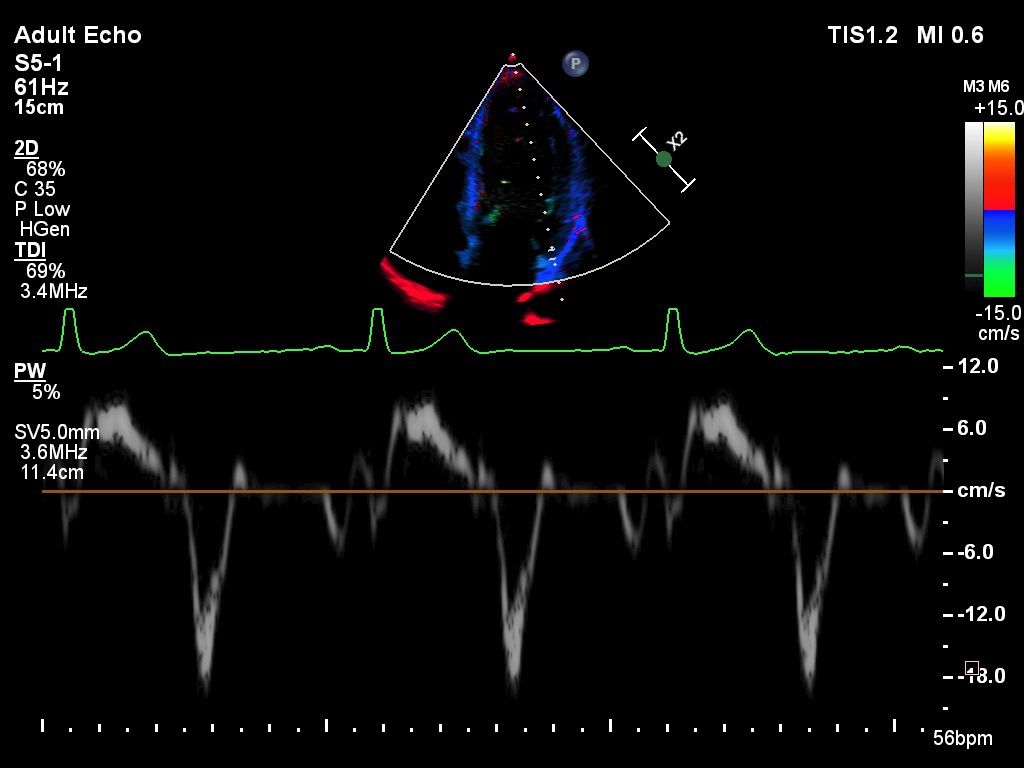

- Кардиология

Функции для кардио-исследований

- TDI - тканевый допплер

- Strain Q - функция для оценки скорости движения стенок миокарда

- A2DQ - автоматическое распознавание границ камер сердца и расчет площади, объема левого желудочка и параметров систолы и диастолы левого желудочка, расчет фракционной площади, фракции выброса, максимальной скорости выброса, максимальной скорости быстрого наполнения и фракции предсердного наполнения

- aCMQ - Анализ параметров общей и конкретной сократимости камер сердца

- CMQ Stress - стресс эхокардиография для оценки глобальной и регионарной сердечной функции в различных состояниях

- Тканевый доплер